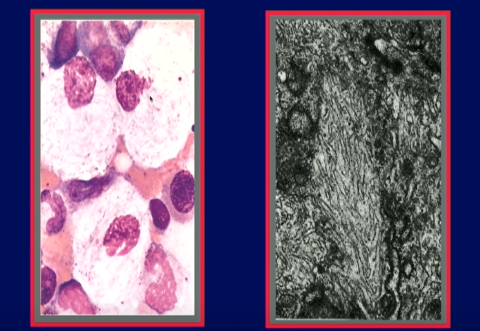

Two microscope images on a dark purple PowerPoint slide. The left image shows white cells in a faint pink background; each cell contains a pinkish-purple nucleus. The grayscale image on the right shows wrinkled, tubular structures in the interior of a cell's lysosome.

Evidence of Gaucher disease shown in the cells in a bone marrow smear (l) and the lysosome of a single cell. At left, the nuclei of the cells (dark pink) are pushed to the side by the lipid-filled lysosomes. These classic “Gaucher cells” have a wrinkled, tissue-paper appearance, as shown by the tubular structures in the lysosome in the second image.